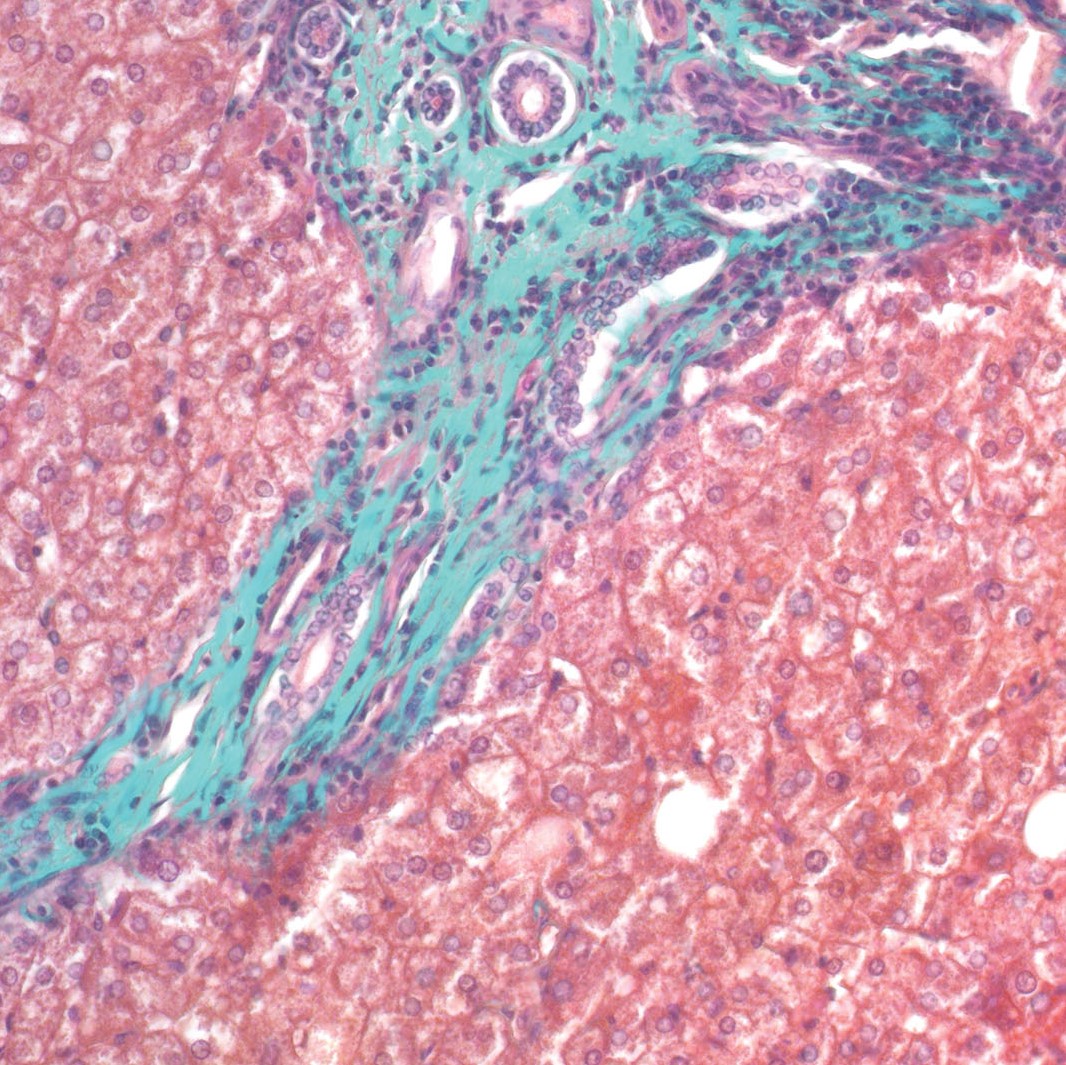

El Kit Tricrómico de Masson-Goldner se utiliza para la visualización de los músculos, las fibras de colágeno, los tejidos conectivos, los gametos, los núcleos, las neurofibrillas, la neuroglía, el colágeno, las fibrillas intracelulares de queratina y la visualización negativa del aparato de Golgi. Representa el método de tinción de fibras musculares y de colágeno en los tejidos durante el cual el colorante Fast Green F.C.F. se une al colágeno haciendo que se vuelva claramente verde. También se utiliza para visualizar el aumento de la acumulación de colágeno asociada al tejido en funcionamiento que se confunde con el tejido cicatricial (diagnóstico de esclerosis hepática), pero también para diferenciar las fibras musculares lisas y los colágenos.

Núcleos - azul-púrpura

Fibras musculares, queratina, citoplasma - rojo brillante

Colágeno, moco - verde

Eritrocitos - rojo-naranja